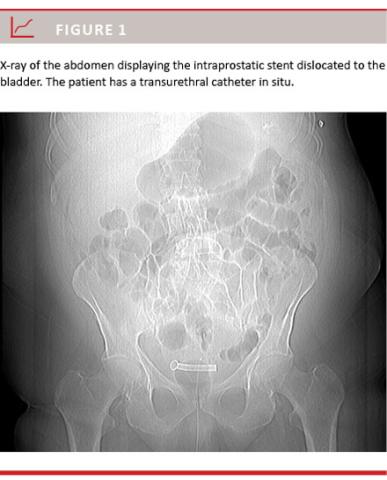

In total, nine stents were removed in seven patients; in three patients the stents were inserted due to their own interest (the patients feared complications to TUR-P, especially in form of erectile dysfunction), and these patients could have been candidates for TUR-P. The stents were removed after 94, 328 and 359 days. Two patients had a subsequent stent inserted. In one patient, the second stent was removed as well after 89 days. One patient with previous TUR-P had the stent removed after six days. One patient with the incontinence technique is mentioned above. The main reasons for removing stents were migration in two cases, infection not responsive to antibiotic in two cases, incontinence in two cases and retention in three cases. Figure 1 shows migration of a stent after insertion of a bladder catheter.